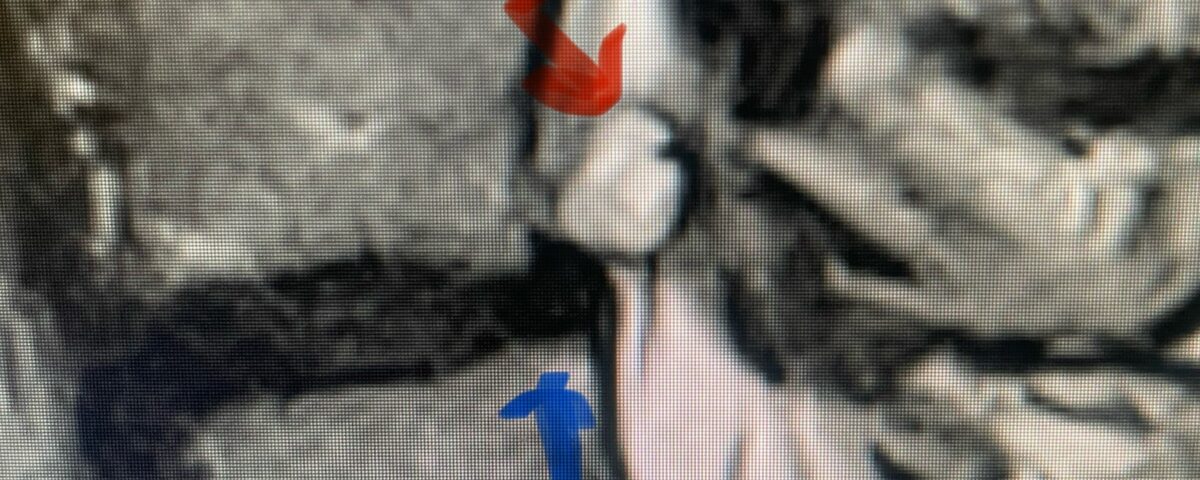

This 50-year-old female with a long history of low back pain and a prior history of multiple lumbar surgeries with instrumentation. She had a L3-5 laminectomy with instrumentation about 7 years prior and now presents with progressive worsening of low back pain. The pain was worse with activity, standing, walking, and prolonged sitting. She had an MRI which showed next segment degeneration at L2-3 with stenosis and the development of a large posteriorly-oriented synovial cyst with thecal sac compression (Fig. 3). The patient failed all means of conservative management including physical therapy and epidurals. We decided to perform an L revision laminectomy to decompress and remove the cyst as well as explore her prior fusion. In this case, again the anterior wall of the sac was completely stuck to the dural membrane. Therefore, we internally decompressed the cyst which was mainly degenerated, necrotic material and removed as much wall of the cyst that could be safely removed. There was some fluid within the cyst. Of note during the dissection of these cysts there is often a release of cyst fluid the patient was well-decompressed. We removed the prior instrumentation and added a new L2-3 construct (Fig. 4). The patient had an uneventful hospital course and was discharged on post op day 2.